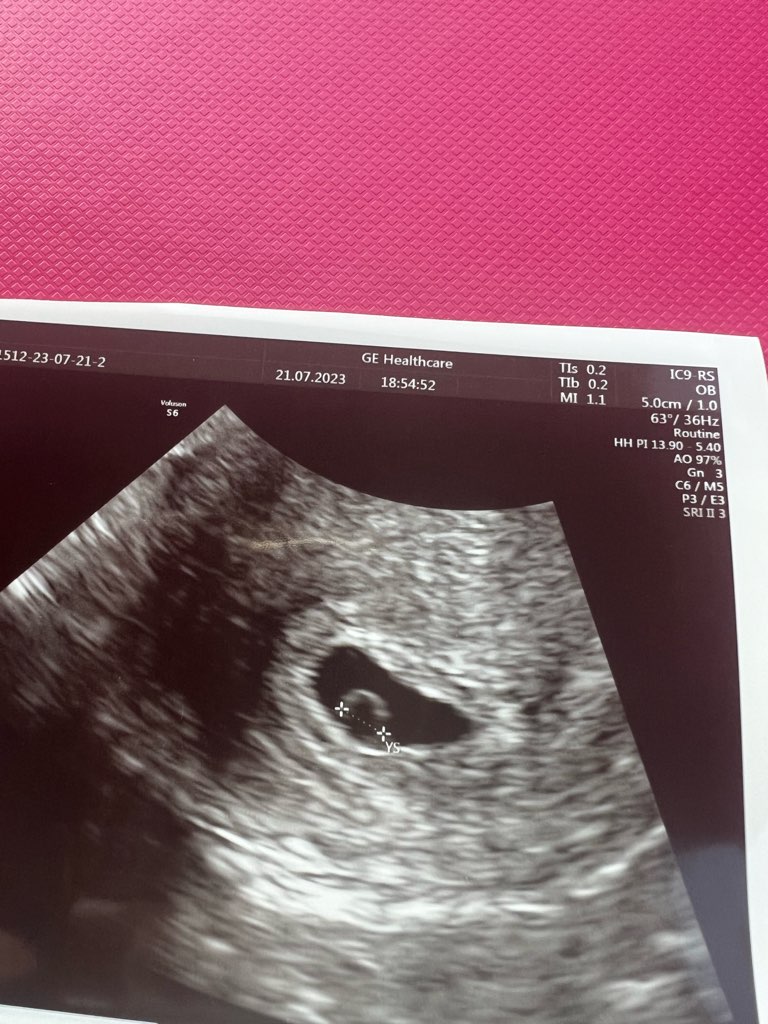

Jest pęcherzyk 0,99cm, ciałko żółte 0,33cm i malusieńki zarodek 0,13